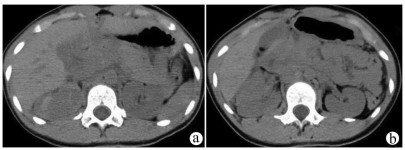

Complete rupture of the pancreas and duodenum caused by car accident in children: A case report

Figures(2)